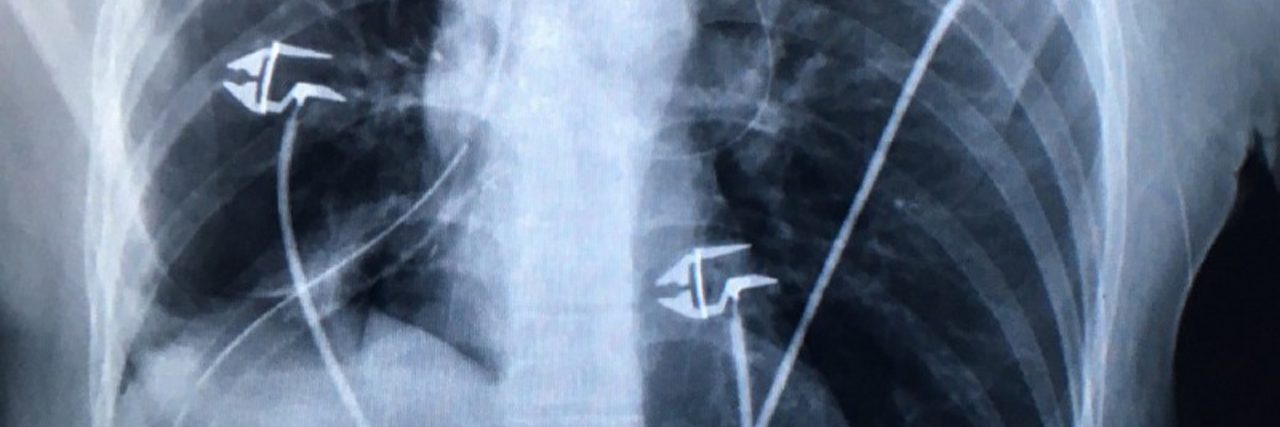

But it isn’t really until you understand what is to happen to your body that everything becomes real. My surgeon drew a diagram of the lungs and a second one explaining the range and types of lung cancers and the associated malignancies.

Turns out my carcinoid tumor (subtly baptized Lil Fucker) — a rare occurrence showing up in only 1- 2 percent of all lung cancers — was hanging out in the airway of the lower and middle lobes in the right lung, the latter of which had already collapsed, its bronchus completely blocked by this shrimp like organism my body birthed. The tumor’s growth was so slow that even as a runner, I couldn’t notice the gradual decline of my lung capacity. And I would have never found it was it not for the occasional cold that kept lingering on for longer than necessary.

I remember the days in the hospital as being quite meaningful. Friends would stream in and out, the room was covered in flowers and a FDNY calendar was an informal barometer for the nurses’ mood. (Also, the hospital might be the only place where a woman in her mid thirties is being told she is young and in great shape.) A “happy button” was keeping any source of pain and panic at bay, needles and tubes perforating the skin, tying you down through a maze, annihilating any idea of mobility. The even rhythm of machines and rituals gave the days a soothing pace, as did watching the lungs’ suddenly precious movement.